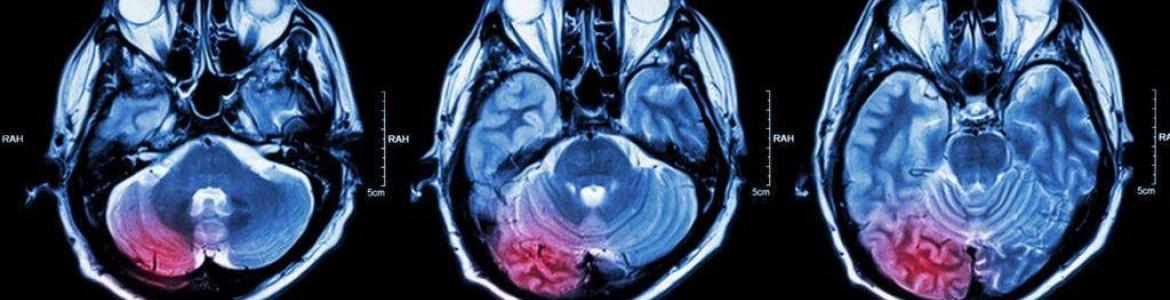

La ciencia frente a los tumores cerebrales

El objetivo es compartir avances científicos, discutir casos clínicos y mejorar la toma de decisiones terapéuticas, algo clave porque el manejo del cáncer cerebral exige integrar cirugía, radioterapia, tratamientos sistémicos y diagnóstico avanzado.